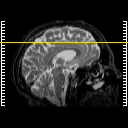

Click on sagittal image to select slice. Click on thin tickmark to change timepoint, or thick tickmark for overlay.